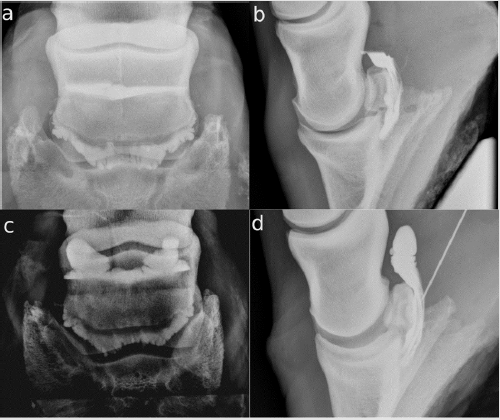

Twenty-three legs were injected. The NB was successfully injected only in 20/23 (86.96 %). In the other three legs, the CM was injected completely palmar to the DDFT (Figure 1b). The NB and the DIP were filled with CM in one horse (4.35 %) (Figure 1a). The DPr-PaDiO CE showed alliterations in 7/9 (77.78 %) legs with a clinical history of lameness. There was CM palmar to the DDFT (Figure 1a) and the NB was filled with CM in 5/20 (25.00 %) legs. The findings are summarized in Table 1. There were two DDFT lesions, one full flexor cortex lesion, three suspected ruptures of the NB and five NB adhesions.

Figure 1:

a. There is contrast medium (CM) in the navicular bursa and the distal interphalangeal joint, and some CM palmar to the deep

digital flexor tendon (DDFT)

b. The injection of the navicular bursa has failed. The CM is completely palmar to the DDFT.